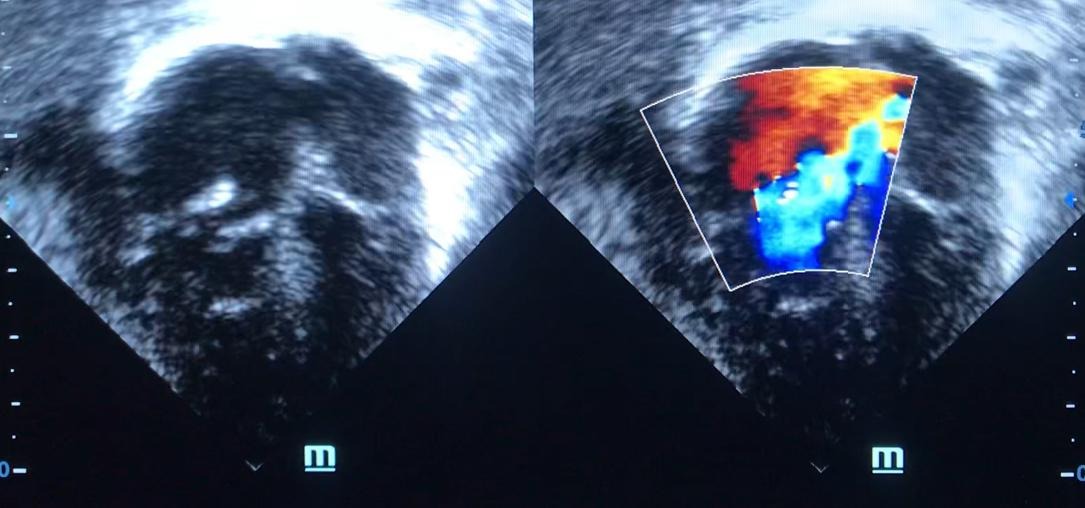

Hi, my name is Dr Cyprian Umeoguaju ( MBBS, MRCPCH), I am soliciting fund for Abubakar Abubakar. I started managing him since he was born. Following his birth, he had a complex congenital heart disease ( tricuspid valve dysplasia) which made him blue since birth. I managed him conservatively and he now needs cardiac surgery as his heart is beginning to fail and his parents cannot afford the huge cost required to help me get cardiac surgical care. I have referred him to FCC Lagos and the cardiac surgical team have carried out preliminary investigation on him and has now planned him for corrective surgery. Abubakar Abubakar needs our help to survive. He has always been a fighter and needs us now to continue to survive. Nothing is too small or too big for his survival. May God meet you at the point of your need as your contribute your resources.